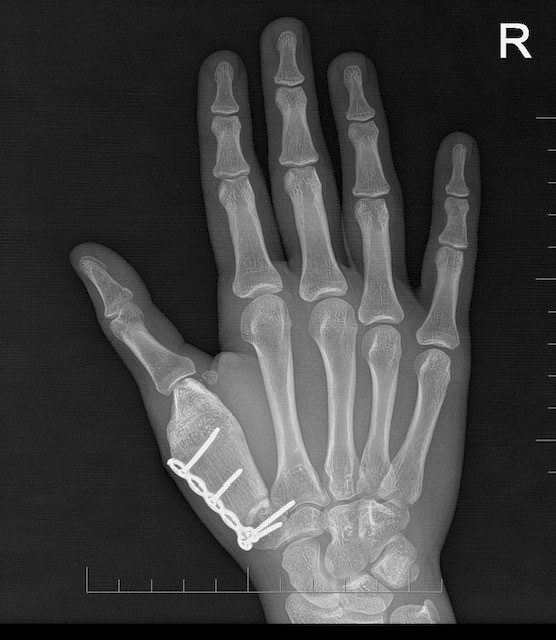

Schválená liečba trvala niekoľko mesiacov, nasledovalo vyšetrenie ruky a na výsledky, ktoré mali rozhodnúť o ďalšom postupe, už všetci netrpezlivo čakali. „Röntgen napokon priniesol dobré správy – nádor sa zmenšil a skalcifikoval. Tým sa však náš boj s touto diagnózou neskončil. Dcéra musela podstúpiť takmer šesťhodinovú operáciu na 1. Ortopedickej klinike vo Fakultnej nemocnici u Svätej Anny v Brne, počas ktorej jej transplantovali kosť v pravej ruke. Keď som napokon videla ten malý palček pravej ruky, ktorý vytŕčal spod sadry, vydýchla som si. Dcéra o ruku neprišla,“ spomína si na tieto dni jej mama.

Transplantovanú kosť telo jej dcéry napokon prijalo a začala sa postupne zrastať, mama hovorí priam o zázraku. „Dcéra bola po transplantácii nesvoja, ustráchaná, bolo jej ťažko a nevoľno. V škole niekoľkokrát vracala, cítila smútok. Palec na pravej ruke stratil v kĺbe ohybnosť, po chemoterapiách bola veľmi oslabená a bojovali sme aj s komplikáciou, že dostala rotavírusovú infekciu, kvôli ktorej jej zlyhávali obličky a musela byť opäť hospitalizovaná. Postupne však prišli lepšie výsledky a lepšie dni,“ dodáva.